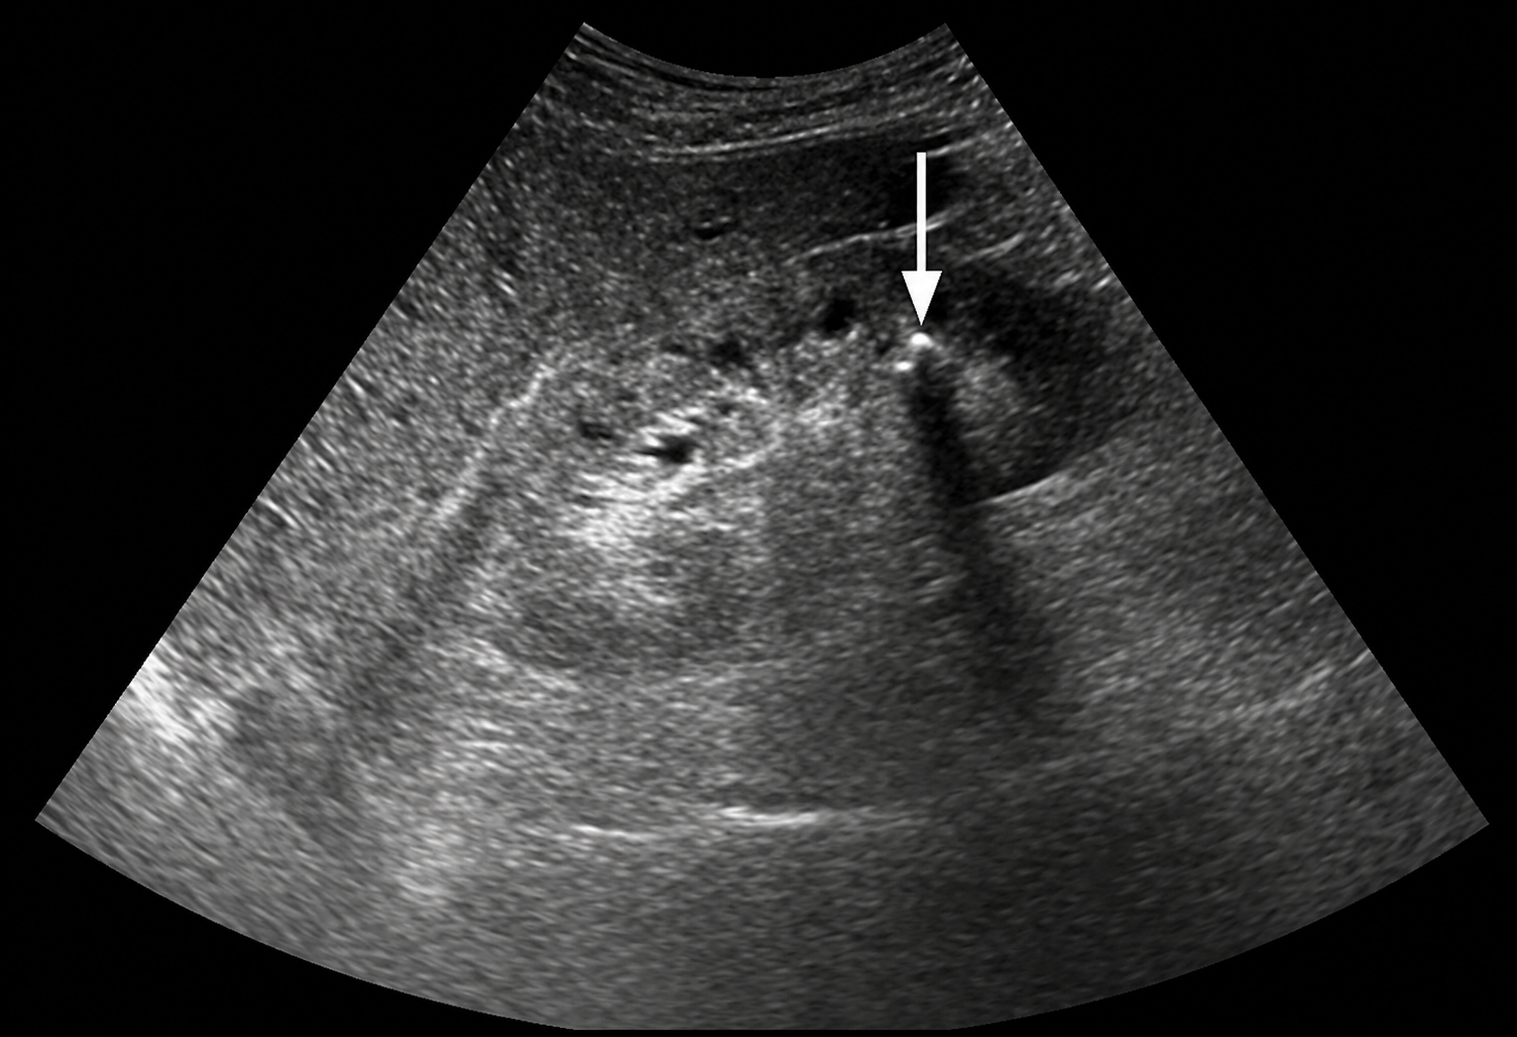

Kết quả xét nghiệm hình ảnh khiến tất cả phải bàng hoàng khi xác nhận sự hiện diện của rất nhiều sỏi trong thận.

Ảnh minh họa